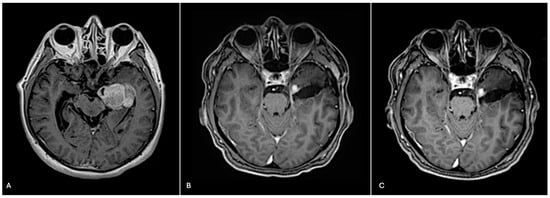

A 72-year-old male presented with a two-day history of altered mental status and emesis secondary to a 4.3 cm enhancing mass in the left temporal region, detected on a brain MRI with and without contrast (Figure 1A). His neurological exam was notable for memory impairment. Following a subtotal resection, which left a residual 1 cm nodule at the medial aspect of the resection cavity, histopathology revealed a high-grade glial neoplasm. In some areas, tumor cells with spindled hyperchromatic nuclei showed a compact growth pattern, interspersed with intervening areas (Figure 2A,B). Rosenthal fibers and eosinophilic granular bodies were absent. Scattered in these regions were bizarre, multinucleated cells with smudgy chromatin. In other areas, tumor cells with round-to-oval nuclei and scant-to-moderate amounts of cytoplasm were embedded in a fibrillary, neuropil-like background, associated with entrapped neurons, increased mitotic activity (at least 6 mitoses per 2 mm2), and incipient microvascular proliferation (Figure 2C). In these infiltrative high-grade areas, geographic necrosis and viable tumor cells surrounding vasculature formed a pseudopapillary architecture (Figure 2D). Tumor cells were positive for GFAP, OLIG2, and synaptophysin (weak, diffuse in high-grade areas, focal in compact areas). Neurofilament staining was negative in compact areas and highlighted entrapped axons in infiltrative high-grade areas. The p53 stain was patchy, suggestive of the wild-type TP53 gene. ATRX was retained in compact areas but was lost in infiltrative high-grade areas. P16 was absent from both regions. The Ki-67 labeling index was low in the compact areas but was estimated at 40% in high-grade areas (Figure 3).

The patient was treated with radiation and concomitant temozolomide. Post-radiation brain MRI showed a stable residual 1 cm enhancing nodule at the medial aspect of the resection cavity (Figure 1B). At the time of publication, he completed 6 cycles of adjuvant temozolomide and remains stable both clinically and radiographically (Figure 1C). Ethical guidelines set out by the Declaration of Helsinki were followed in the preparation of this report, and the patient provided written consent.

Figure 1. Pre-surgical, post-surgical, and post-2 cycles of temozolomide imaging. (A) Pre-surgical axial T1 brain MRI with contrast reveals a 4.3 cm enhancing mass. (B) Post-radiation axial T1 brain MRI with contrast reveals a residual 1 cm enhancing nodule at the medial aspect of the resection cavity. (C) Following two cycles of adjuvant temozolomide, axial T1 brain MRI with contrast reveals a stable residual 1 cm enhancing nodule at the medial aspect of the resection cavity.